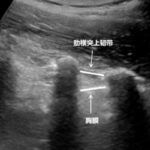

植入式中心静脉导管系统(输液港)是一种为长期输液及化疗患者提供安全静脉通路的装置,可显著提升生活质量与治疗便利性。本文系统梳理输液港维护中易被忽视的细节,如无损伤针使用、纱布放置、穿刺方向、回血评估、封管液浓度及造影剂推注注意事项,帮助医护人员规范操作,延长装置寿命并降低感染与堵管风险。 Read More... "经输液港输液,6 个最容易被忽略的冷知识"